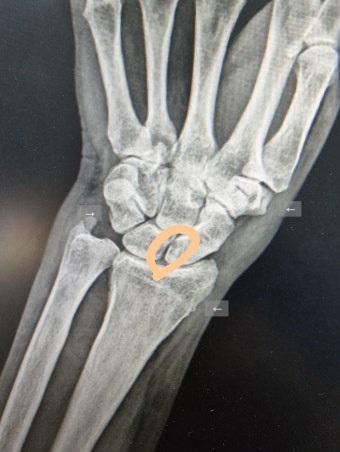

제가 사진에서 동그라미 친 부분이 많이 벌어져 있다? 하더라고요 그걸 치료하려면 주사치료를 해야 하는데 이 병은 재발이 심해서 한 번이 아니고 여러 번 맞아야 한다 그래서 더 걱정이 돼요 혹시 주사가 많이 아플까요? 병명은 그냥 인대 늘어남 일까요?

사진상 표시된 부위는 손목 인대나 관절간격 문제로 보이는 경우가 많습니다. 말씀처럼 단순 인대 늘어남부터 손목인대 손상까지 다양하게 진단될수 있습니다. 주사치료는 보통 염증을 줄이거나 통증을 완화하기 위해 시행합니다. 주사 자체는 따끔한 정도의 통증은 있지만 참기 힘들 정도는 아닌 경우가 대부분입니다. 특히 국소마취를 같이 하거나 짧은 시간에 끝나기 때문에 부담이 크진 않습니다. 다만 손목은 신경이 예민한 부위라 맞을 때 약간 찌릿한 느낌이 있을수 있습니다. 여러번 맞는 이뉴는 인대회보과 통증조절을 단계적으로 하기 위함입니다. 너무 걱정하기보다 치료과정이라고 생각하시고 진행하셔도 괜찮습니다!

동그라미 부위가 벌어져 보인다면 단순 인대 늘어남보다 "손목 인대 손상(불안정성)" 가능성이 있습니다.

• 사진에서 표시하신 부위는 해부학적으로 주상골–월상골 사이, 즉 주상월상 인대 손상(Scapholunate ligament injury) 가능성이 있는 위치입니다. 단순 “인대 늘어남”보다는 부분 파열 또는 불안정성까지 포함된 개념일 수 있습니다. 이 경우 X-ray에서 간격이 벌어져 보일 수 있습니다.

통증과 관련해서 말씀드리면, 손목 관절 내 주사는 일반적으로 “참을 수 있는 수준의 통증”으로 평가됩니다. 바늘이 들어갈 때 따끔한 통증이 있고, 약물이 들어갈 때 약간의 압박감이나 뻐근함이 동반됩니다. 다만 손목은 구조가 좁고 신경 분포가 밀집되어 있어 개인에 따라 통증이 다소 예민하게 느껴질 수 있습니다. 대부분의 경우 시술 전 국소마취를 함께 시행하기 때문에 실제 주사 통증은 상당히 완화됩니다. 시술 시간은 보통 1분에서 2분 내외로 짧습니다.

주사 치료의 목적은 염증 감소와 통증 조절입니다. 대표적으로 스테로이드 주사를 사용합니다. 다만 주상월상 인대 손상에서 주사는 구조적 회복을 만드는 치료는 아니며, 증상 완화 목적이기 때문에 재발이나 반복 시술이 필요한 경우가 있습니다. 반복 주사는 조직 약화를 유발할 가능성이 있어 일반적으로 횟수 제한을 두고 시행합니다.

임상적으로 중요한 점은 다음입니다. 단순 염좌 수준이면 보존적 치료(보조기, 휴식, 약물)로 호전되지만, 인대 불안정성이 명확하면 추후 관절 퇴행성 변화로 진행할 수 있어 추가 평가가 필요합니다. 필요 시 자기공명영상(MRI) 또는 관절경 평가를 통해 손상 정도를 확인합니다. 불안정성이 지속되면 수술적 치료를 고려하기도 합니다.

정리하면, 주사 자체의 통증은 대체로 견딜 수 있는 수준이며 마취로 조절 가능합니다. 다만 현재 상태가 단순 염좌인지, 인대 부분 파열 이상인지에 따라 치료 전략이 달라지므로 정확한 평가가 중요합니다.